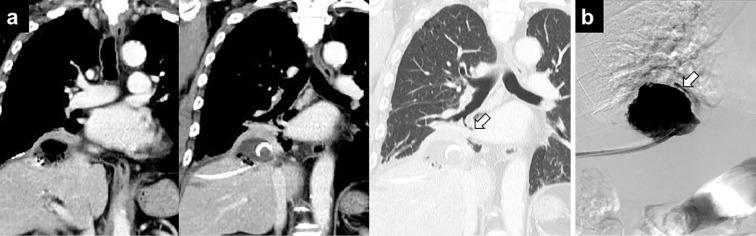

经皮射频消融治疗肝细胞癌后并发肝脓肿和胆支气管瘘的支气管腔内 Watanabe 分叉管置入术。

Endobronchial Watanabe Spigot Placement for Hepatic Abscess and Bronchobiliary Fistula Following Radiofrequency Ablation for Hepatocellular Carcinoma.

A bronchobiliary fistula (BBF) is an uncommon but severe complication after radiofrequency ablation (RFA). However, the definitive salvage methods are controversial. We herein report a patient with hepatocellular carcinoma with hepatic abscess and BBF following RFA. We also review previous reports of BBF after RFA. The patient was a man in his 70s who underwent RFA for recurrent hepatocellular carcinoma in the subphrenic area. Despite percutaneous transhepatic abscess drainage, bilioptysis persisted. Finally, the BBF was occluded with an endobronchial Watanabe spigot under fiber-optic bronchoscopy. Placing an endobronchial Watanabe spigot should be considered as a salvage therapy for refractory BBF following RFA.

摘要

支气管胆瘘(BBF)是射频消融(RFA)后一种罕见但严重的并发症。然而,明确的补救方法存在争议。我们在此报告一例 RFA 后肝脓肿和 BBF 的肝细胞癌患者。我们还回顾了 RFA 后 BBF 的以往报告。患者为 70 多岁男性,因膈下区复发性肝细胞癌接受 RFA 治疗。尽管经皮经肝脓肿引流,但仍存在胆汁漏。最终,在纤维支气管镜下通过支气管内渡边塞子闭塞 BBF。对于 RFA 后难治性 BBF,放置支气管内渡边塞子应被视为一种补救治疗方法。